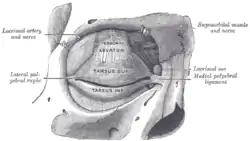

The tarsi and their ligaments. Right eye; front view. | |

The lateral palpebral raphe is a ligamentous band near the eye. Its existence is contentious, and many sources describe it as the continuation of nearby muscles. It is formed from the lateral ends of the orbicularis oculi muscle. It connects the orbicularis oculi muscle, the frontosphenoidal process of the zygomatic bone, and the tarsi of the eyelids.

The lateral palpebral raphe is formed from the lateral ends of the orbicularis oculi muscle.[1][2] It may also be formed from the pretarsal muscles of the eyelids.[3][4] It is attached to the margin of the frontosphenoidal process of the zygomatic bone. It passes towards the midline to the lateral commissure of the eyelids. Here, it divides into two slips, which are attached to the margins of the respective tarsi of the eyelids.

The lateral palpebral raphe is a much weaker structure than the medial palpebral ligament on the other side of the eyelids.